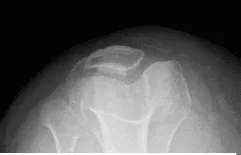

Horizonte de Patella